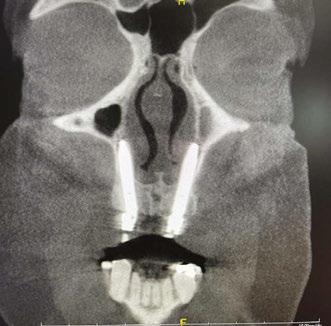

Due to the atrophic nature of the maxilla, treatment following the PATZi protocol was planned.6,17,20 CBCT evaluation revealed pterygomaxillary bone appropriate for pterygoid implants allowing for posterior arch support and cantilever elimination. The zygomas were of adequate height and width to accommodate multiple zygomatic implant fixtures bilaterally. PLACATE guidelines were used to evaluate the patient for potential treatment with transnasal implants. With Simmen 3 nasolacrimal canal classification, ≥ 3 mm of prelacrimal bone, ≥2 mm subnasal bone, and ≤ 25 mm to the Z-point, the patient satisfied all PLACATE parameters. Accordingly, a treatment plan of bilateral pterygoid, single zygomatic, and transnasal implants was agreed upon.

Following PATZi, anterior support was sought next. As such, the nasal mucosa was elevated to expose the floor of the nasal cavity and the bone of the inferior conchae. A pair of 25 mm transnasal implants were placed, and each achieved high insertion torque of 45+ Ncm (Figures 9-11). Continuing with the PATZi protocol and treatment plan, 42.5 mm long zygomatic implants were placed in both zygomas. The zygomatic implants were placed using an extrasinus approach and both achieved insertion torque of 45+Ncm. Buccal fat pedicles were advanced bilaterally to cover extrasinus portions of the zygomatic implants, and flap closure was achieved with 4-0 chromic gut suture. The patient was immediately temporized with a screw-retained transitional bridge (Figure 12), and a final zirconia restoration was delivered after 8 months of healing (Figure 13).

Figure 10 (left): CBCT slice (coronal view) of transnasal dental implants engaging the Z-point. Figure 11 (middle): CBCT slice (sagittal view) of transnasal dental implant engaging prelacrimal bone ventral to the nasolacrimal duct. Figure 12 (right): 3-dimensional CBCT rendering of patient treated with transnasal, zygomatic, and pterygoid dental implants via the PATZi protocol